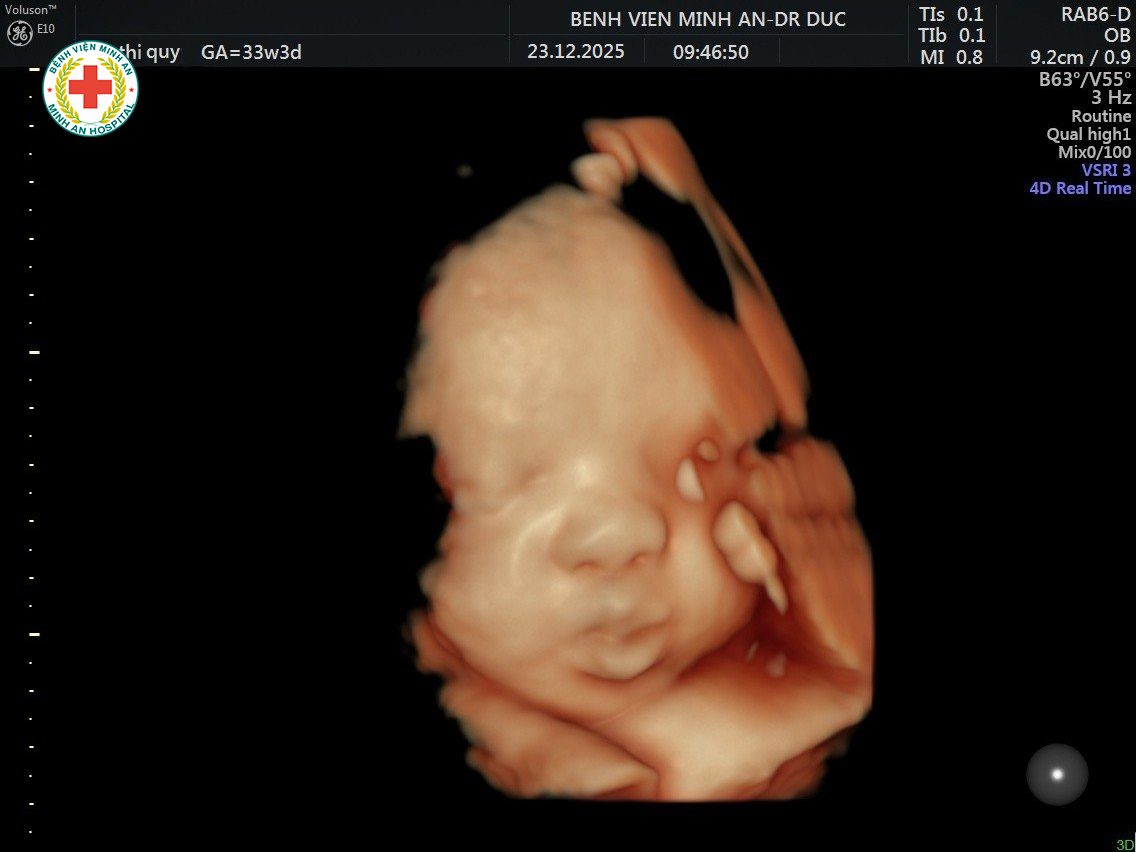

Siêu âm 5D thai nhi – Yêu ngay từ cái nhìn đầu tiên

Mỗi lần đầu dò siêu âm nhẹ nhàng lướt qua bụng mẹ, là một lần cả gia đình được “nhìn thấy” điều quý giá nhất: gương mặt bầu bĩnh, chiếc mũi xinh, đôi môi chúm chím, từng biểu cảm rất thật của con yêu…